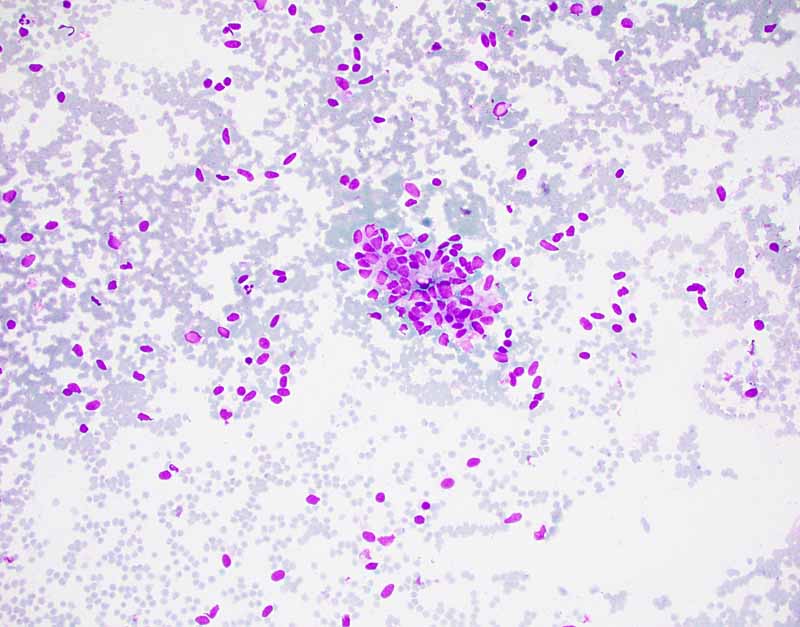

For Comparison: The following images were obtained from the FNA and core biopsy of a monophasic spindle cell synovial sarcoma. In general, the nuclei are rather monotonous and small. They are typically elongated and are very adhesive to each other. Typically, the amount of cytoplasm is minimal or most of the cells are naked nuclei. This case has SS18 rearrangment on FISH.

1.

DiffQuick

2.

3.

PAP Stain

4.

5.

Cytospin

6.

7. 8.